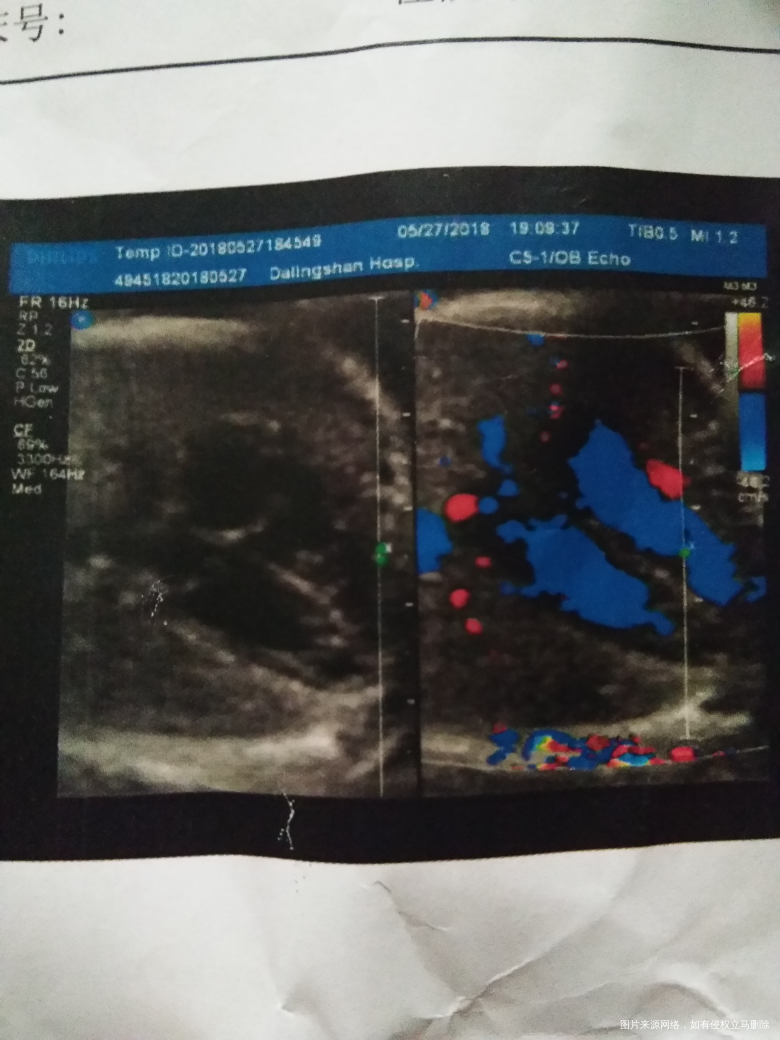

以下是检查内容求医生解答,谢谢